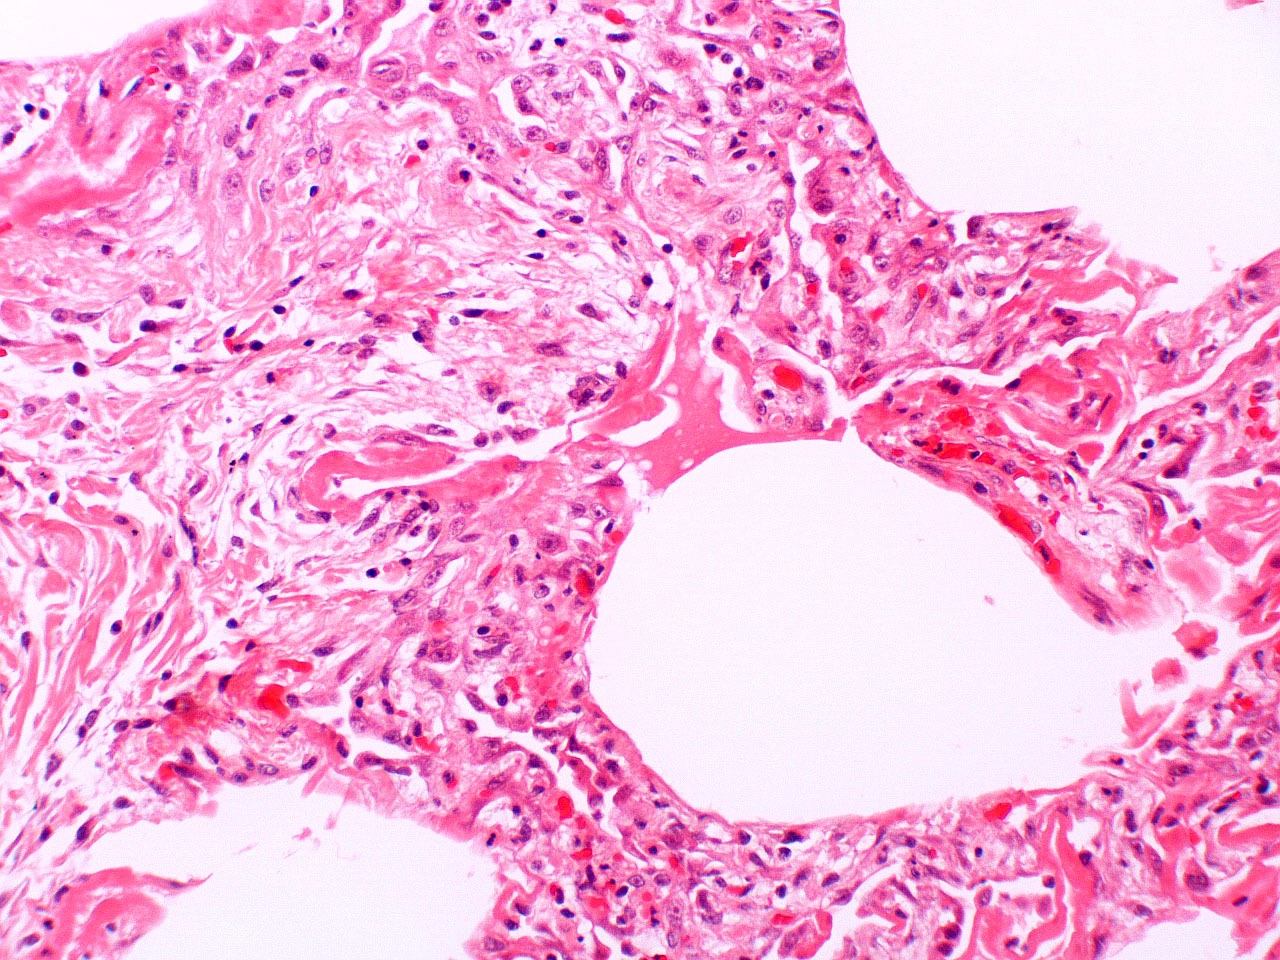

Microscopic (histologic) description

- Histopathology of DAD progresses from exudative (acute) phase through proliferative / organizing (subacute) phase to chronic fibrotic phase roughly corresponding to the period of ARDS (Am J Pathol 1976;85:209, Arch Pathol Lab Med 2010;134:719, Clin Chest Med 2000;21:435, N Engl J Med 2000;342:1334)

- Exudative (acute) phase

- Alveolar change

- Hyaline membranes on alveolar duct or sacs

- Interstitial and intra-alveolar edema

- Collapsed alveoli

- Epithelial change

- Denudation and necrosis of type I pneumocytes

- Vascular change

- Necrosis of endothelial cells

- Neutrophil aggregation

- Microthromboemboli

- Hemorrhage

- Alveolar change

Microscopic (histologic) images

Contributed by Akira Yoshikawa, M.D. and Yale Rosen, M.D.